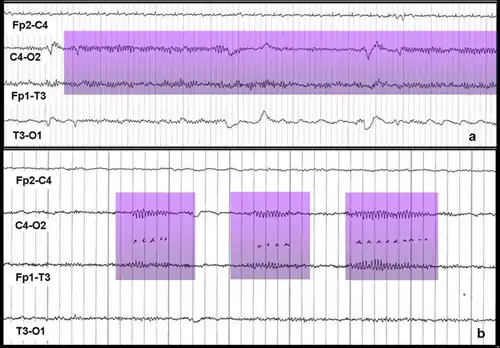

Мю-ритм (μ-ритм, роландический ритм, сенсомоторный ритм, аркоидный (arceau) ритм, аркообразный (wicket) ритм, гребенчатый ритм, дугообразный ритм) — ритм головного мозга — периодические колебания биопотенциалов в сенсомоторной области коры головного мозга на частоте 8 — 13 Гц (чаще всего 9 — 11 Гц). Эти колебания могут быть зарегистрированы методами электроэнцефалографии (ЭЭГ), магнитоэнцефалографии (МЭГ), или электрокортикографии (ЭКОГ). Наиболее выражен в состоянии физического покоя. В отличие от альфа-ритма, который возникает на аналогичной частоте в задней части головы над зрительной корой также в состоянии покоя, мю-ритм локализован над моторной корой. У человека подавление мю-ритма происходит, когда он или она выполняет какое-либо движение или, после определённой тренировки, когда он или она визуализирует (представляет) выполнение движений. Это подавление называется десинхронизация (уменьшение амплитуды сигнала), потому что причиной появления ритмических паттернов на ЭЭГ является синхронная активность большого числа нейронов. Кроме того, мю-ритм подавляется когда человек наблюдает за выполнением движений другого человека. Рамачандран и его коллеги предположили, что это является признаком того, что зеркальная нейронная система участвует в подавлении мю-ритма[1][2], однако, есть и противники этой теории[3]. Мю-ритм представляет интерес для множества учёных. Например, при изучении развития нервной системы, интерес представляют подробности формирования мю-ритма в младенчестве и детстве и его роль в процессах обучения[4]. Поскольку некоторые исследователи считают, что расстройства аутистического спектра (РАС) во многом связаны с изменениями в системе зеркальных нейронов[1][5][6], и что подавление мю-ритма отражает активность зеркальных нейронов[2], многие из этих учёных заинтересованы в изучении мю-ритма у людей с расстройствами аутистического спектра. Мю-ритм широко используется при построении мозг-компьютерных интерфейсов (МКИ). С развитием МКИ систем, врачи надеются дать людям с тяжёлыми инвалидностями новые способы коммуникации, средства для манипулирования и перемещения в пространстве[7].

Интерфейсы мозг-компьютер (ИМК) — активно развивающаяся технология, которая, как полагают, однажды сможет дать бо́льшую независимость людям с инвалидностями. Предполагается, что эти технологии смогут помогать людям почти полностью или даже полностью парализованным, например с такими заболеваниями как тетраплегия (квадриплегия) или боковым амиотрофическим склерозом. ИМК могут помочь таким больным в общении или даже позволят контролировать движение инвалидных кресел и нейропротезов[7][17]. Одним из типов МКИ является интерфейс, использующий событийно-связанную десинхронизацию мю-ритма для управления компьютером[7]. Этот метод мониторинга активности мозга основан на том факте, что когда группа нейронов находится в состоянии покоя они, как правило, возбуждаются синхронно. Если оператор МКИ мысленно представит движение («событие»), произойдёт десинхронизация (связанная с «событием»). Нейроны, которые до этого возбуждались синхронно, приобретут свои индивидуальные, не похожие друг на друга паттерны возбуждения. Это приведёт к уменьшению амплитуды регистрируемого сигнала, которое может быть зафиксировано и проанализировано при помощи компьютера. Операторы подобных МКИ тренируются визуализировать движения ногами, руками и/или языком. Эти части тела имеют удалённые друг от друга проекционные зоны коры головного мозга и поэтому их легче всего отличить друг от друга на основе записей электроэнцефалограммы (ЭЭГ) или электрокортикограммы (ЭКоГ) с электродов размещённых над моторной корой[7][18]. Событийно-связанная десинхронизация может быть использована вместе с другими методами мониторинга электрической активности мозга, позволяя создавать гибридные ИМК, которые часто оказываются более эффективными, чем ИМК использующие только один метод мониторинга[7][18].

Мю-ритм впервые был описан Гасто в 1952 году[19] и был охарактеризован им как «the rythme en arceau» за характерную аркообразную форму волн. Позднее в электроэнцефалографической литературе мю-ритм получил название роландического или центрального альфа ритма, поскольку его фокус располагается рядом с центральной (роландовой) бороздой коры головного мозга, а частота колебаний совпадает с частотой затылочного альфа-ритма[16]. Однако, долгое время ему не придавали большого значения так как считалось, что он встречается лишь у небольшой части людей[2]. Применение современных техник анализа сигнала, таких как анализ независимых компонент, доказало наличие мю-ритма у большинства здоровых людей[20].

В отличие от α-ритма, μ-ритм активируется во время психической нагрузки и психического напряжения. Выполнение любых движений независимо от их структуры, силовой, временной, пространственных характеристик всегда сопровождается блокированием μ-ритма. Ритм также блокируется мысленным представлением движения, состоянием готовности к движению или тактильной стимуляцией. Мало реагирует на воздействия других раздражений, например, световых и звуковых[2]. Выражен у слепых, компенсирующих потерю зрения развитием тактильного и двигательного исследования среды, у которых он встречается в три раза чаще по сравнению со зрячими. Также μ-ритм выражен у спортсменов (в пять раз чаще, чем у лиц, не занимающихся спортом)[21].